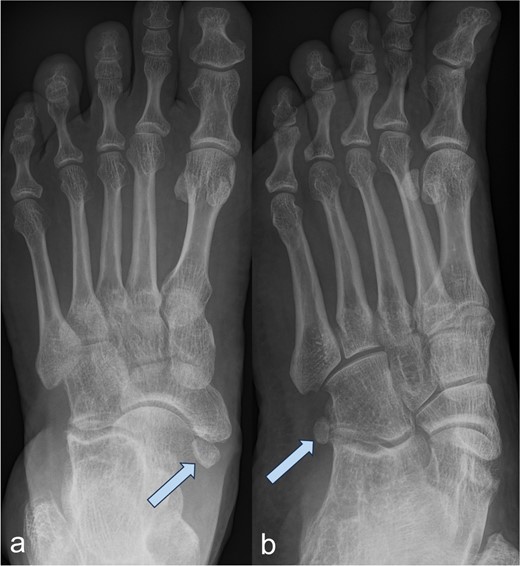

A 53-year-old man with a body mass index of 22.3 kg/m2 reported severe, load-dependent pain (6 out of 10 on the VAS) in the left foot, which had increased over the past two months. Light jogging as a recreational sport was no longer possible due to pain, and no trauma was recalled. Clinically, there was a mild pes planovalgus, with slight swelling and warmth medioplantarly and distal to the medial malleolus along the course of the tibialis posterior tendon. A marked point tenderness was noted, and forced dorsiflexion was severely painful. Conventional radiographs showed a triangular Type II Os tibiale externum at the typical site, measuring approximately 10.5 x 6 mm (Fig. 1a and b). Additional CT imaging in the axial plane with coronal reconstruction and subsequent 3D reconstruction (Fig. 2a and b) revealed a Type II Os tibiale externum with a distinct synchondrosis gap to the navicular bone. An MRI showed central inflammatory reaction in the synchondrosis and significant perifocal soft tissue edema of the Os tibiale externum with involvement of the tibialis posterior tendon, with no tendon rupture detected (Fig. 3a–d).

Image of the Os tibiale externum Type II in the coronal reformatted CT scan (a) and in the 3D representation (b); the ossicle is marked with an arrow.